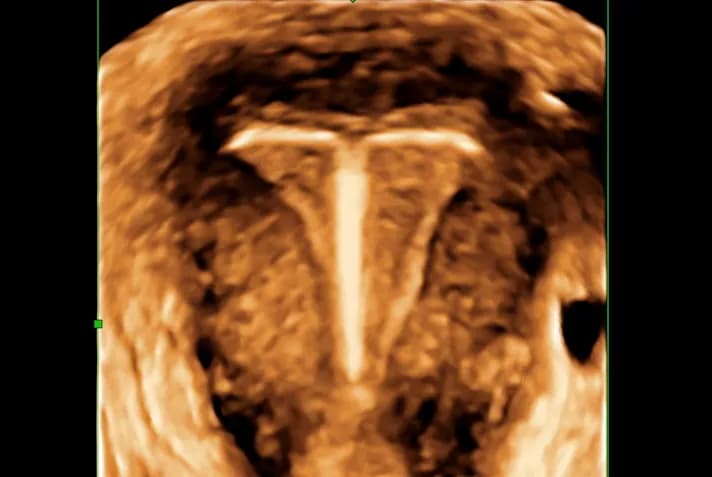

Podczas wizyty u lekarza w przypadku podejrzenia przesunięcia wkładki domacicznej, pacjentki mogą spodziewać się szczegółowego wywiadu medycznego oraz badania ginekologicznego. Lekarz zapyta o objawy, takie jak silne bóle brzucha, obfite krwawienia czy wydzielina o nieprzyjemnym zapachu. Ważne jest, aby być szczerym i dokładnym w odpowiedziach, ponieważ to pomoże lekarzowi postawić właściwą diagnozę.

W trakcie konsultacji lekarz może zlecić dodatkowe badania, takie jak ultrasonografia, aby ocenić położenie wkładki oraz sprawdzić, czy nie doszło do uszkodzenia tkanek. W niektórych przypadkach konieczne może być wykonanie badań laboratoryjnych, aby wykluczyć infekcje. Te kroki są kluczowe dla zapewnienia odpowiedniego leczenia i poprawy zdrowia pacjentki.